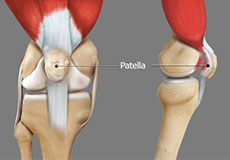

The knee is a hinge joint made up of two bones, the thighbone (femur) and shinbone (tibia). There are two round knobs at the end of the femur called femoral condyles that articulate with the flat surface of the tibia called the tibial plateau. The tibial plateau on the inside of the leg is called the medial tibial plateau and on the outside of the leg, the lateral tibial plateau.

The two femoral condyles form a groove on the front (anterior) side of the knee called the patellofemoral groove. A small bone called the patella sits in this groove and forms the kneecap. It acts as a shield and protects the knee joint from direct trauma.

Patella Fracture

The kneecap or patella forms a part of the knee joint. It is present at the front of the knee, protecting the knee and providing attachment to various muscle groups of the thigh and leg.